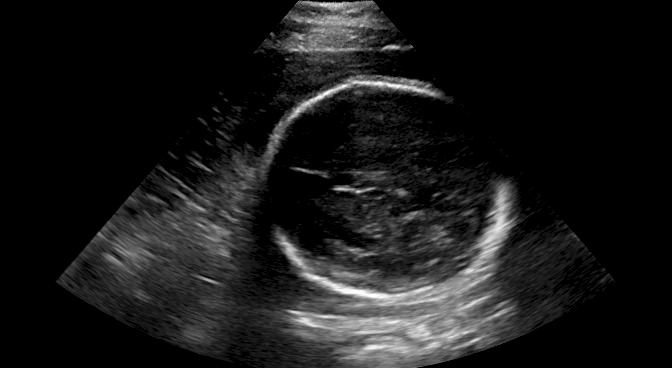

Sound-opaque occluders, including bones and calcified tissues, block the propagation of sound waves by strongly absorbing or reflecting sound waves during scanning. The regions behind these sound-opaque occluders return little to no reflections to the US transducer. Thus these areas have low intensity but very high acoustic impedance gradients at their boundaries (e.g. Fig. 1(a) left column). Reducing acoustic shadows and correct interpretation of images containing shadows rely heavily on sonographer experience. Experienced sonographers avoid shadows by moving the probe to a more preferable viewing direction during scanning or, if no shadow-free viewing direction can be found, a mental map is compounded with iterative acquisitions from different orientations.

We propose a novel method based on convolutional neural networks (CNNs) to automatically estimate pixel-wise confidence maps of acoustic shadows in 2D US images. Our method learns an initial latent space of shadow regions from images consisting of multiple anatomies and with global image-level labels (“has shadow” and “shadow-free”), e.g. Fig. 1(a). The basic latent space is then estimated by learning from fewer images of a single anatomy (fetal brain) with coarse pixel-wise shadow annotations (approximately of the images with global image-level labels), e.g. Fig. 1(b). The resulting latent space is then refined by learning shadow intensity distributions using fetal brain images so that the latent space is suitable for confidence estimation of shadow regions. By using shadow intensity information, our method can detect more shadow regions than the coarse manual segmentation, especially relatively weak shadow regions.